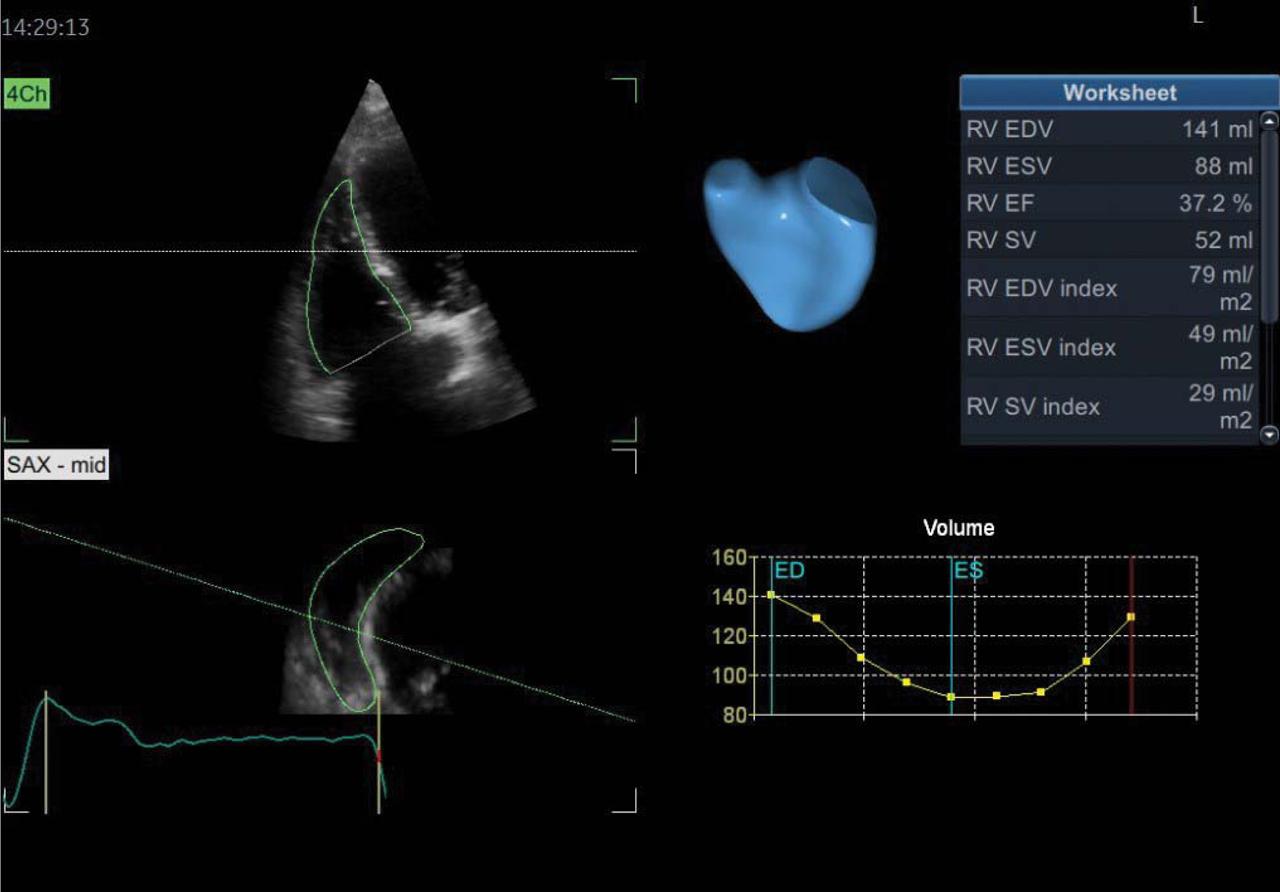

Figure 3